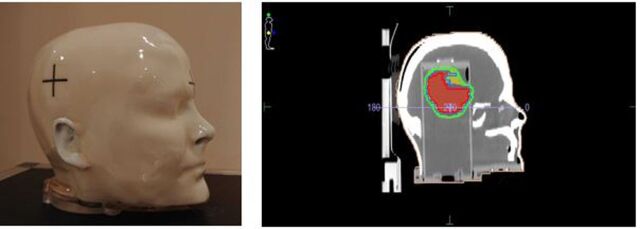

Methods: Using cross-sectional analysis, data were collected from the linear accelerator of twenty patients undergoing (H&N) radiotherapy treatments using the Volumetric Modulated Arc Therapy (VMAT) modality from June 2019 to October 2023 at Gleneagles Hospital Penang, Penang, Malaysia. EPIgray® software reconstructed the delivered dose based on EPID images. These reconstructed doses were compared with the planned doses to evaluate dose accuracy, specifically looking at how many patient doses fell within the set tolerance range. In addition, RTsafe PseudoPatient™ phantom was involved in this study, and the reconstructed dose with EPIgray® was compared with the delivered dose and was established as a benchmark for accuracy.